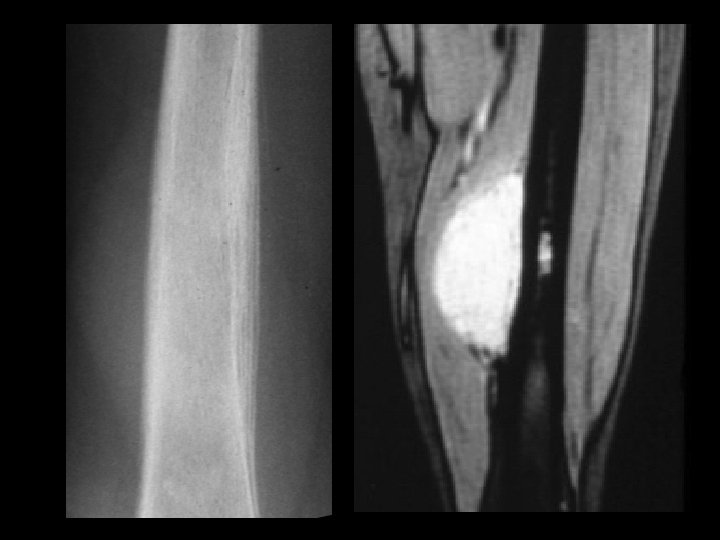

Aneurysmal bone cyst • Findings: – Lucent end of bone lesion in the proximal tibia – Slightly expansile, mild periosteal reaction – Fluid-fluid level on MRI • ddx: – Giant cell tumor – Unicameral bone cyst – Fibrous dysplasia – Chondroblastoma (rare)